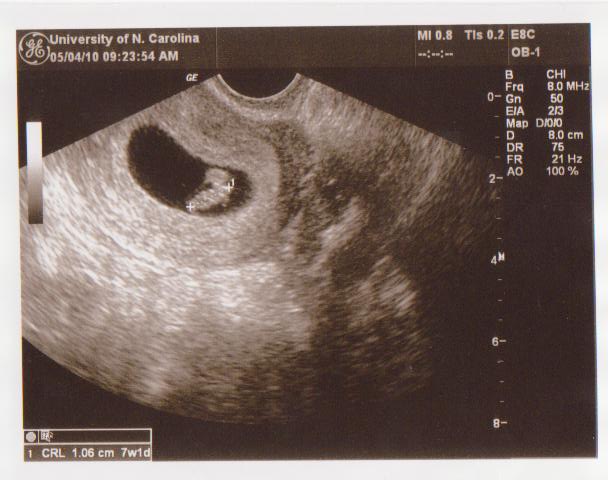

7 Week Ultrasound Heartbeat 153

7 week ultrasound heartbeat 153. A slow fetal heart rate is termed a fetal bradycardia and is usually defined as 1. Ivf baby 7 week ultrasound. Through an ultrasound scan at 7 weeks twin or multiple pregnancy can be detected in the form of multiple gestational sacs.

At seven weeks the embryos heartbeat can be detected through an ultrasound scan. Fhr around 170 bpm may be classified as borderline fetal tachycardia. In other words this myth is busted.

We have a heart beat. Sometimes the babys position in the womb may prevent you from hearing the heartbeat in. A heartbeat is the first sign of a healthy and live foetus.